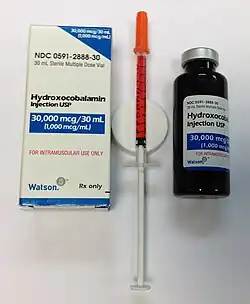

Treatment is by vitamin B12 supplementation, either by mouth or by injection.[3] Initially in high daily doses, followed by less frequent lower doses, as the condition improves.[3] If a reversible cause is found, that cause should be corrected if possible.[11] If no reversible cause is found, or when found it cannot be eliminated, lifelong vitamin B12 administration is usually recommended.[12] A nasal spray is also available.[2] Vitamin B12 deficiency is preventable with supplements, which are recommended for pregnant vegetarians and vegans, and not harmful in others.[2] Risk of toxicity due to vitamin B12 is low.[2]

Treatment should take into account the cause and severity of the condition.[6] Treatment is done by vitamin B12 supplementation, either by mouth or by injection,[3] initially in high daily doses, followed by less frequent lower doses, as the condition improves.[3] If a reversible cause is found, that cause should be corrected if possible.[11] If no reversible cause is found, or when found it cannot be eliminated, lifelong vitamin B12 administration is usually recommended.[12] More serious vitamin B12 deficiency requires injections initially.[3] A 2019 study suggested that oral B12 is inferior to B12 injections in severe cases, as "there is no proof in large prospective, double-blind studies that oral supplementation is as effective in reducing symptoms associated with vitamin B12 deficiency as parenteral treatment."[152]